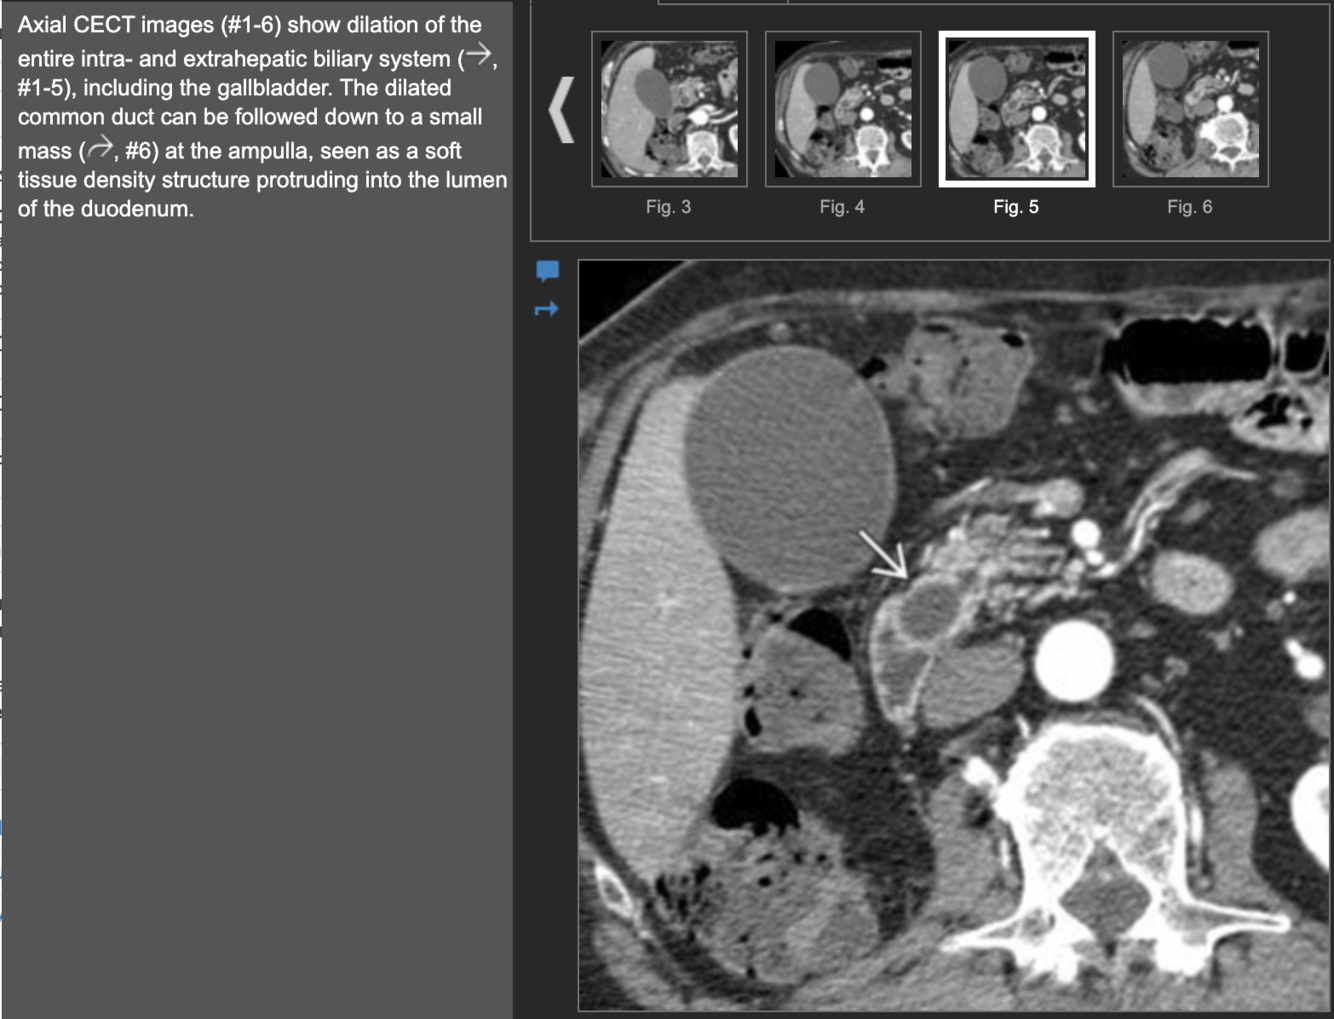

Dilated ducts Dx

Dx?

Dx: type 4A choledochal cyst.